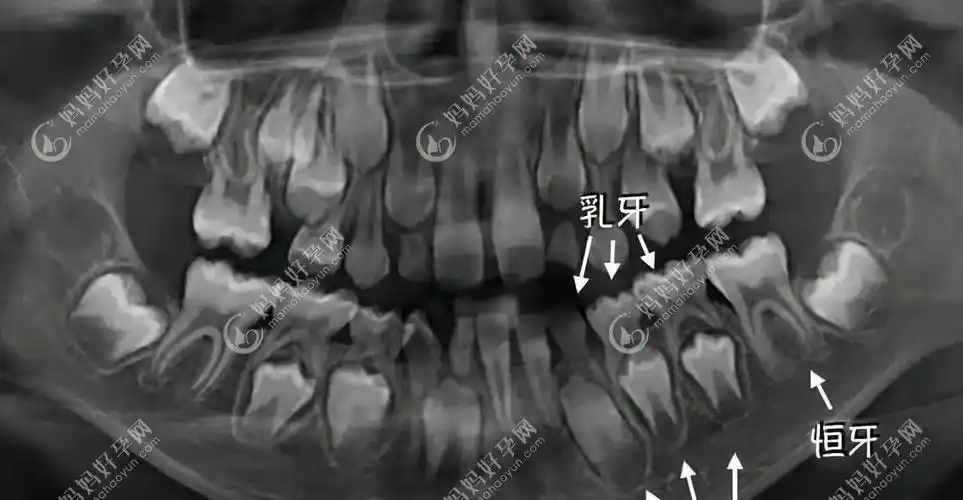

恒牙牙胚错位

白色表示乳牙,浅黄色表示恒牙

正常情况下,恒牙胚位于乳牙根的靠近舌头的那一侧,恒牙在萌出过程中

的话,也会使乳牙的根尖与牙槽骨发生粘连,难以自然脱落,等恒牙萌出时

应该是有乳牙未脱落,一般乳牙未脱落是因为恒牙牙胚的缺失,所以拔除后